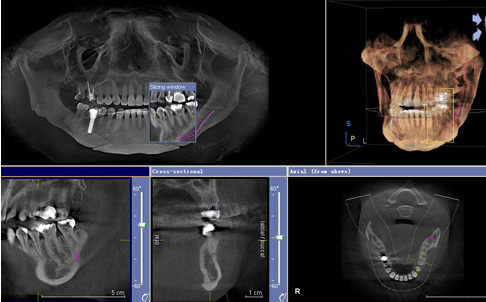

第一步、口腔CT术前检查/拍片

茁悦口腔斥巨资引进的口腔CT能够帮助医生详细、全面、清晰的了解患者口腔内部情况,并且在可视的环境下进行手术,使种植牙齿更安全、更有效。

第二步、种植方案设计

采用口腔CT+全景诊断后,进行全数字化电脑设计诊疗方案,种植牙植入的角度、深度都有详细的设计数据。采用准确的外科导航系统,根据事先设计好的角度、深度进行种植,避开血管神经,同时确保种植体的稳固和种植方案的安全。